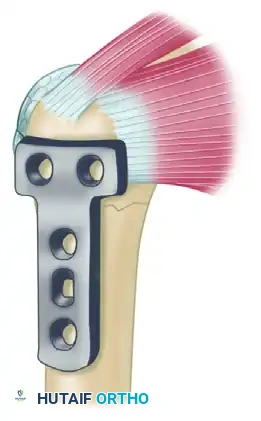

To counteract these deforming forces, Healy, Jupiter, Kristiansen, and White described a highly effective combination technique utilizing a buttress plate augmented with heavy tension band wiring.

Biomechanical Rationale:

The supraspinatus and infraspinatus exert a powerful superior and posterior pull on the greater tuberosity fragment. By weaving a heavy nonabsorbable suture through the rotator cuff tendon insertions and anchoring it directly to the plate, the surgeon neutralizes the muscular pull. This converts the distracting forces into compressive forces across the fracture site and protects the proximal metaphyseal screws from catastrophic pullout.

Step 2: Following debridement of the nonunion and bone grafting, a T-plate or proximal humeral locking plate is applied to the lateral aspect of the humerus to provide a rigid buttress.

Step 3: A heavy, nonabsorbable suture (e.g., #5 FiberWire) is woven through the rotator cuff utilizing a Krackow stitch configuration. The suture is then passed through the proximal holes of the plate and tied securely in a figure-of-eight fashion, effectively neutralizing the pull of the rotator cuff on the proximal fragment.